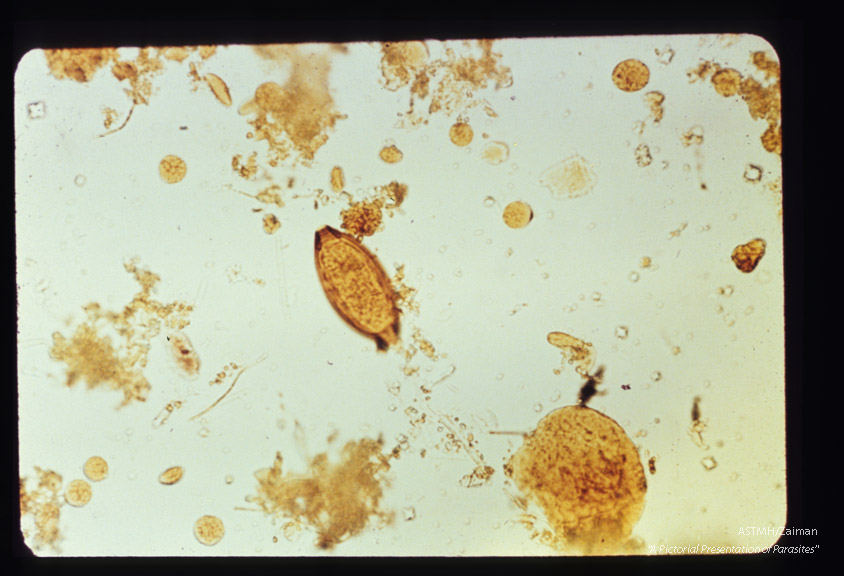

Egg in stool, iodine stained.

Trichuris trlchlura

Description: Egg in stool, iodine stained.